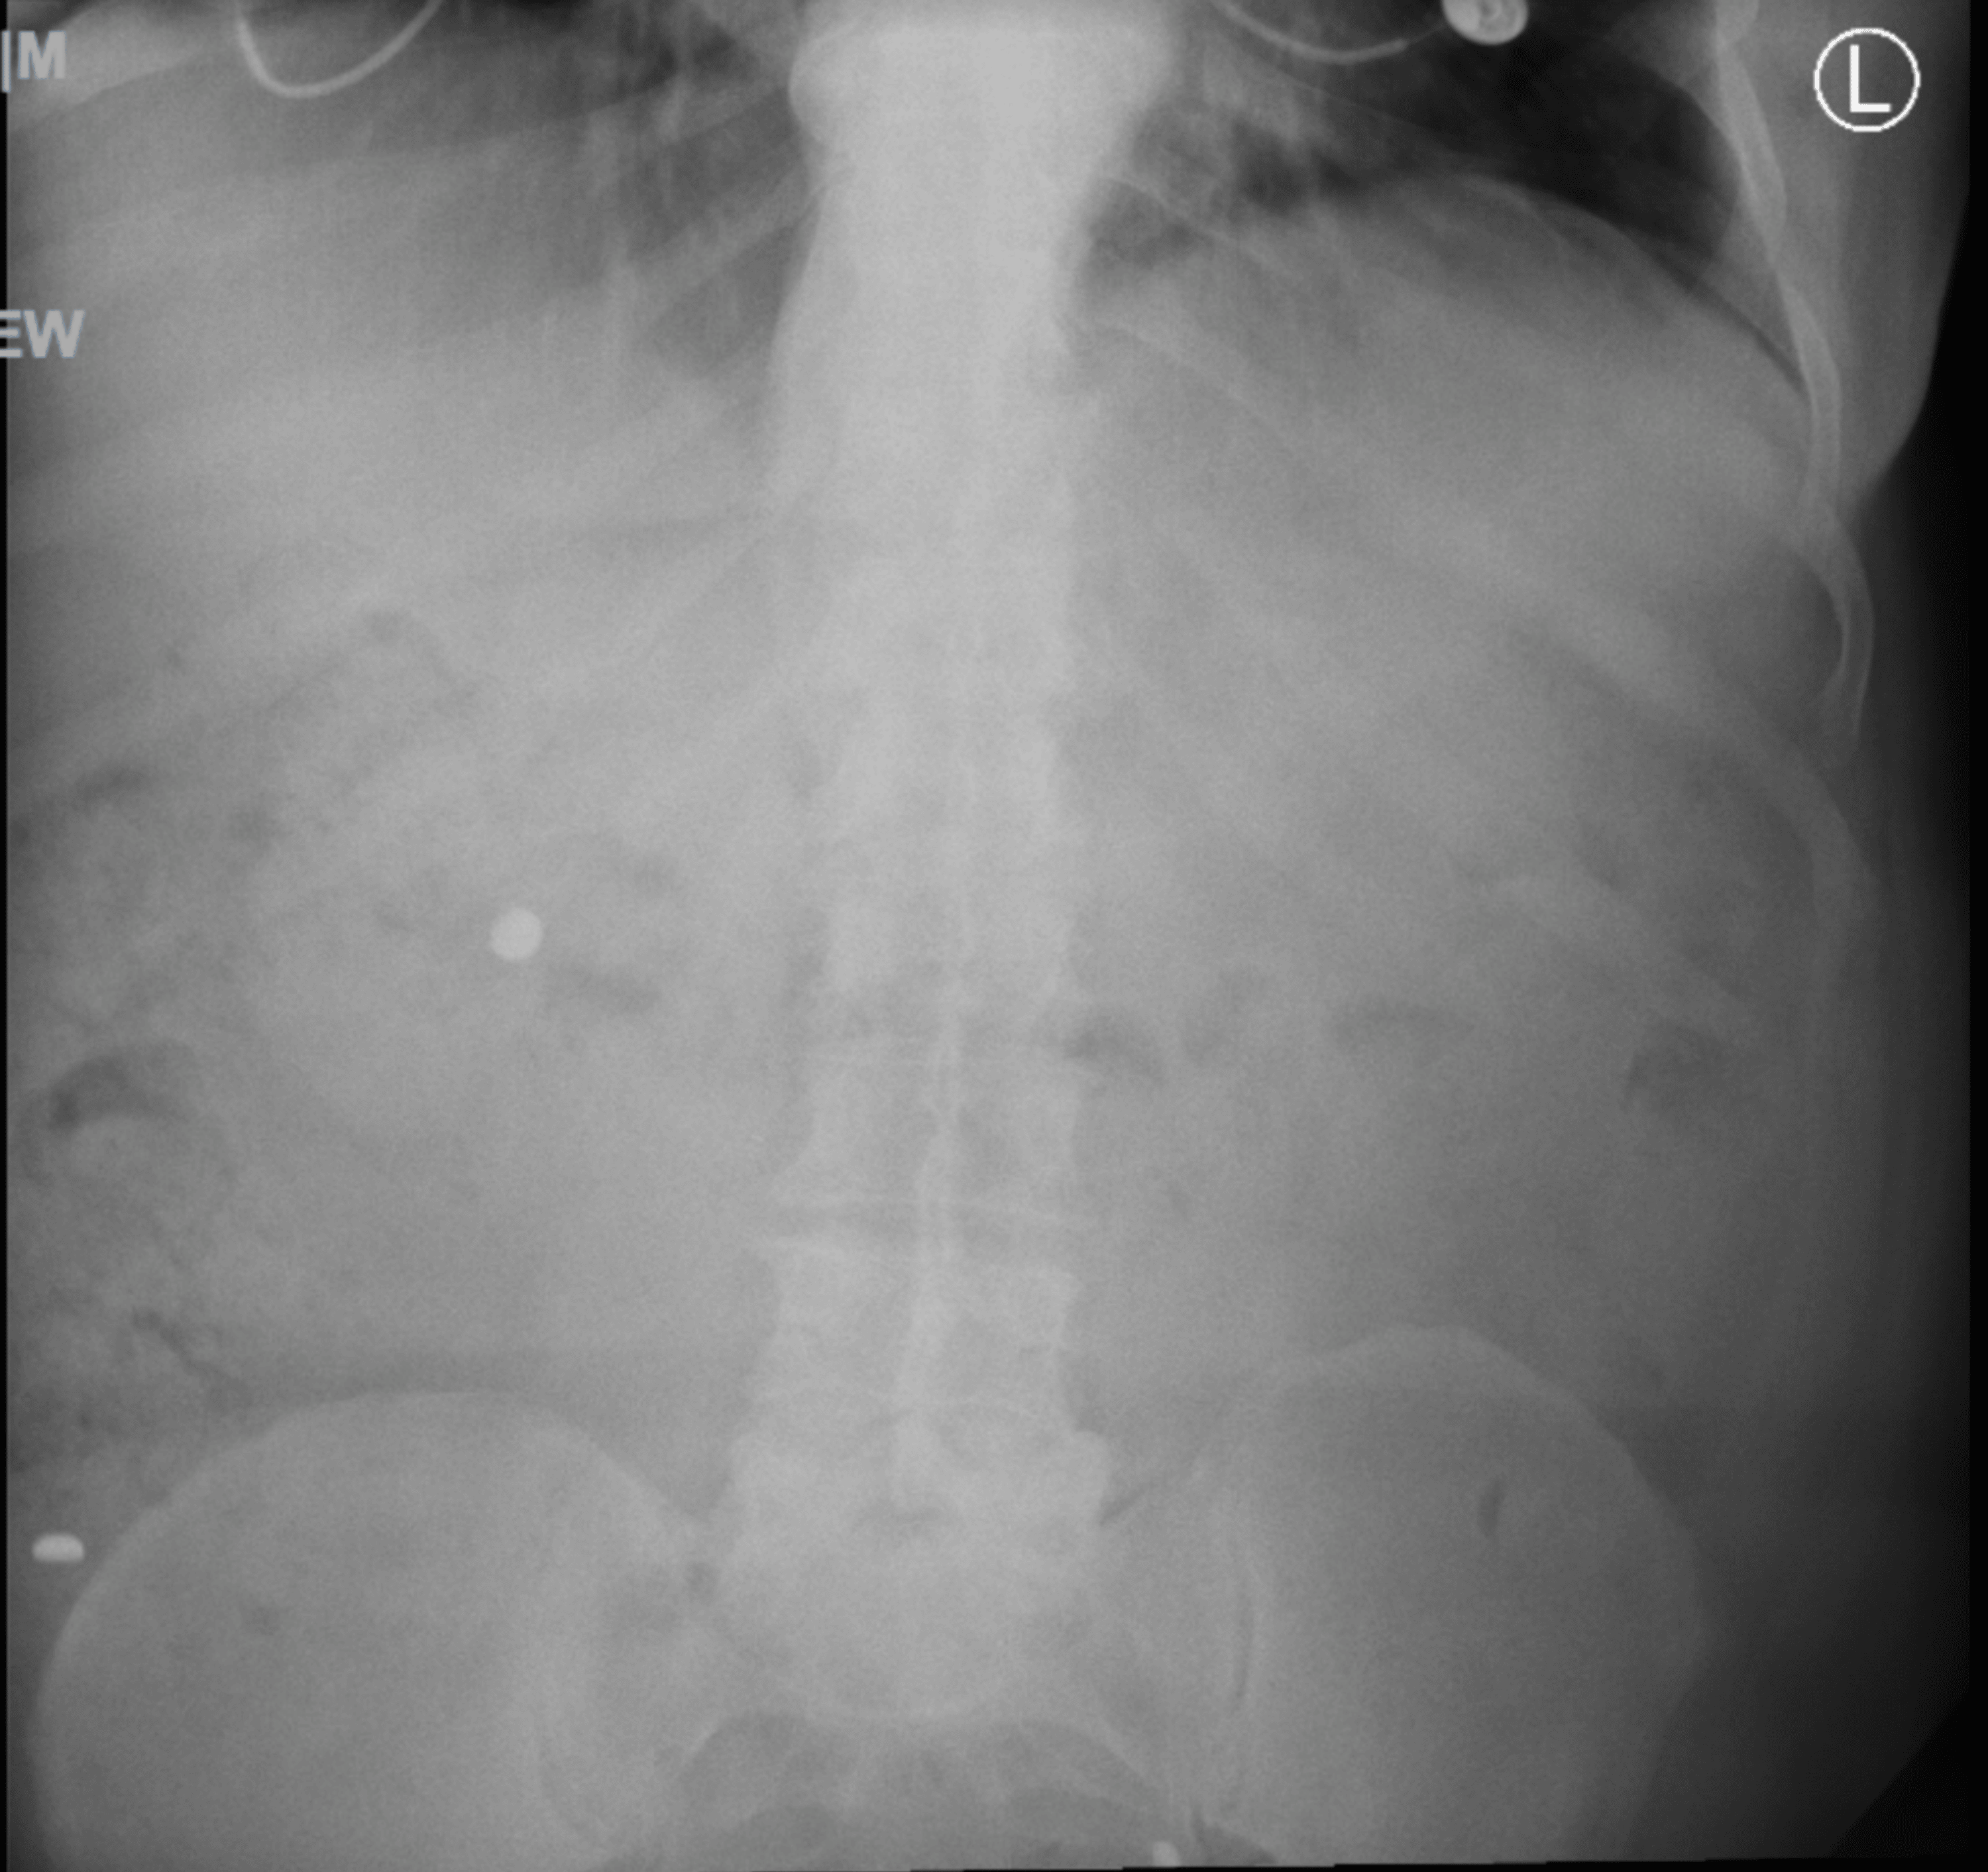

From www.cureus.com

Ingestion of 14 Hearing Aid Batteries in an Adult Patient Cureus Hearing Aid Battery Ingestion Avoid these ineffective, unnecessary or. Button battery ingestion affects all age groups, although most cases involve children under the age of six who mistake the battery for a sweet,. Avoid storing or leaving batteries. They are commonly used in watches and hearing aids. Many cases of accidental battery poisoning have occurred from people who mistakenly ingested a hearing. Button batteries. Hearing Aid Battery Ingestion.